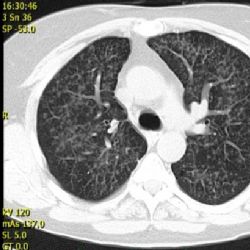

Pacientům s rakovinou plic se otevírají možnosti nové léčby, která se zaměřuje na posílení jejich imunity v boji se zhoubným nádorem. Imunoterapii považují lékaři za začátek nové éry v léčbě nemoci, která ročně v České republice postihne 6500 lidí. Protože u většiny pacientů dochází k odhalení nemoci až v posledním stadiu, valná většina z nich jí také podlehne.